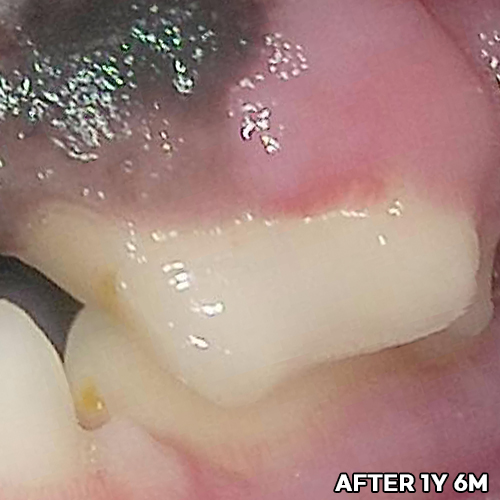

치아뿌리까지 파절된 강아지어금니 빨갛게 부어오른 잇몸치료~ 2년 뒤에 재생된 잇몸뼈 CT로 확인! 모든 동물병원에서 발치하자고 했지만 힐링힐스동물치과병원에서 되살려진 어금니!